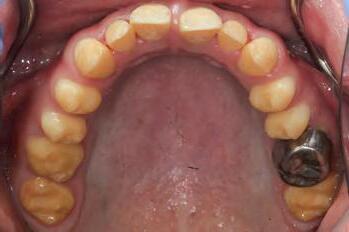

The patient was an 18-year-old male with a confirmed family history of Xlinked AI, who was otherwise in good health and non-smoking. Upon initial clinical presentation, a low-caries-risk, complete adult dentition from second molar to second molar was present, which was globally affected by pitted, hypoplastic and hypomineralised AI, dento-alveolar disproportion and an unusual generalised open occlusion, characterised by one occlusal contact at the right first molar region in the maximum intercuspation position (MIP). Historical paediatric management of the dentition involved placement of stainless steel crowns at the first permanent molar sites to protect the emerging dentition from post-eruptive breakdown and loss of occlusovertical dimension during the mixed dentition phase.6 On adult presentation, all but the UR6 stainless steel crown remained intact. Oral hygiene was poor, with evidence of plaque-induced chronic gingivitis (Figure 1). The patient reported experiencing severe, widespread hypersensitivity upon hot, cold, osmotic and masticatory stimuli, and feeling aesthetically self-conscious. The patient was seeking comprehensive fixed prosthodontic care and was well informed about the nature of such treatment, having witnessed his elder siblings undergo similar treatment.

1: The patient’s initial situation on clinical presentation to the tertiary care referral centre. The dentition is globally af fected by amelogenesis imperfecta, associated with dentoalveolar disproportion and an unusual presentation of open occlusion.